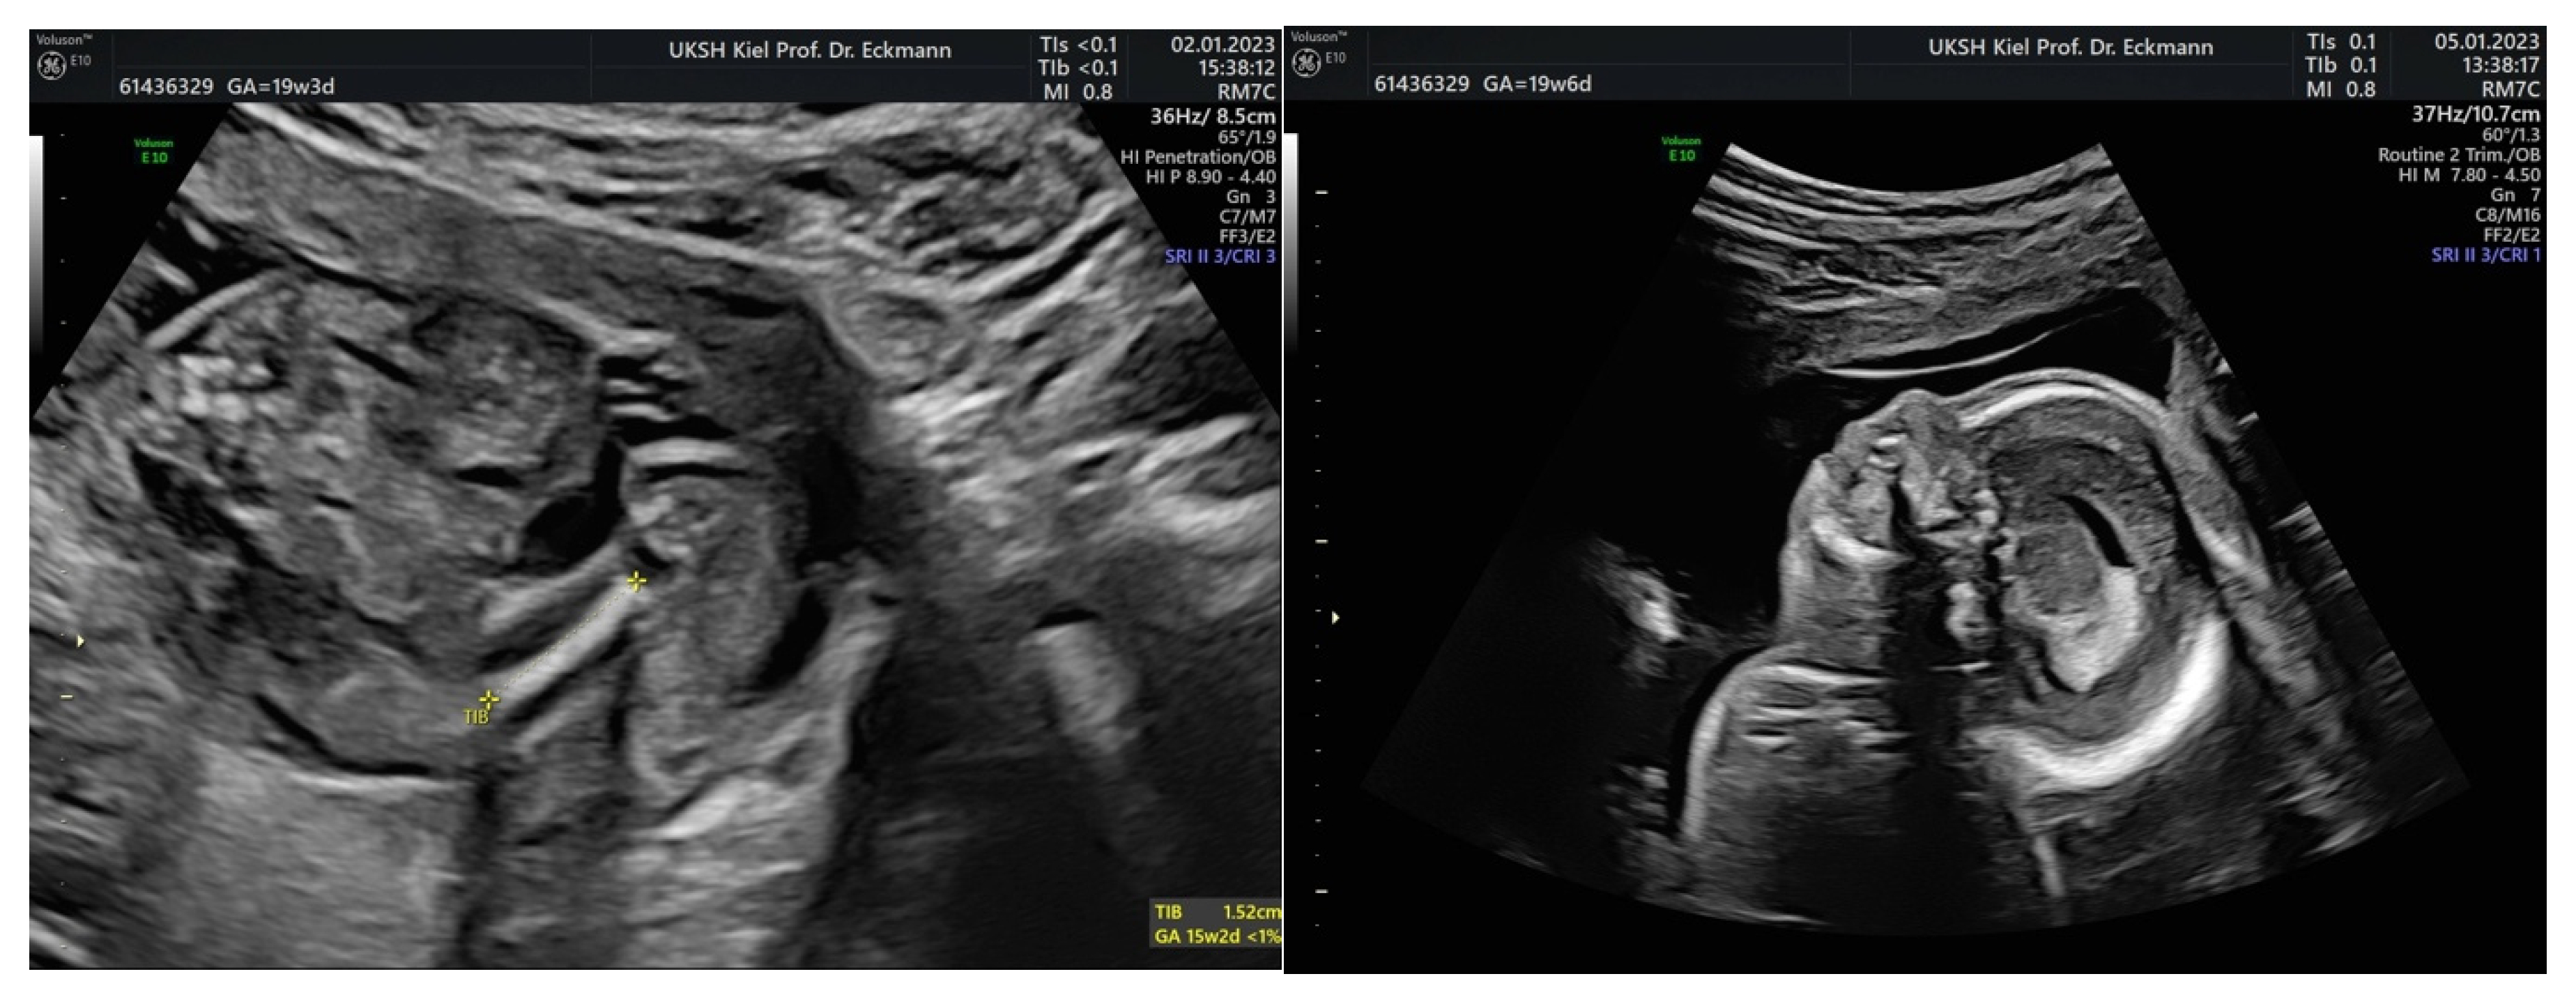

3.3.2. Fetal Growth Restriction

3.3.3. Urogenital Malformations